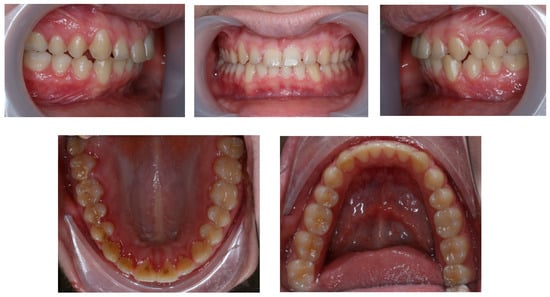

Intraoral examination reveals the achievement of many planned objectives, namely correction of the deep bite, improvement of molar and canine relation on both sides, flattening the curve of Spee, correction of the midlines, and spacing correction (Figure 6).

Figure 6. Post-treatment intraoral photos (the upper line—right, mid, and left occlusion, the lower line—upper arch and lower arch forms).